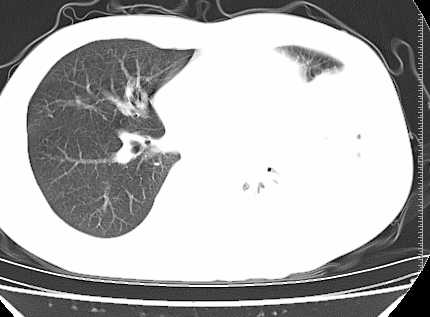

二周前患者无明显诱因出现咳嗽,多为刺激性干嗽,无咯血,伴心悸,低热,夜间无明显盗汗,消瘦明显

年龄?左侧胸腔中量积液,左下肺见有较多斑片状和大片状影,伴有支气管充气征,考虑:1、左下肺炎;2、结核。肿瘤可以基本排除。

考虑:1、左侧中量胸腔积液伴左肺下叶肺膨胀不全、炎症。

2、心包积液。

左下肺见有较多斑片状和大片状影,支气管通畅,左侧胸腔积液,考虑:左下肺炎伴胸腔积液

左侧中量胸腔积液伴左肺下叶肺膨胀不全、上肺外围多个小囊样腺泡样病灶。考虑化脓炎症。

心包积液没有,纵隔积液。

左肺舌叶及下叶见斑片状,大片状高密度影并相应处胸膜及心包不规则增厚,左肺下叶膨胀不全。右肺未见异常,双肺段以上支气管通畅。纵隔左移,其内未见明显肿大淋巴结。左侧胸腔积液。

1.考虑:左肺化脓性炎症。2.左侧胸腔积液(中等量)。3.心包炎症。